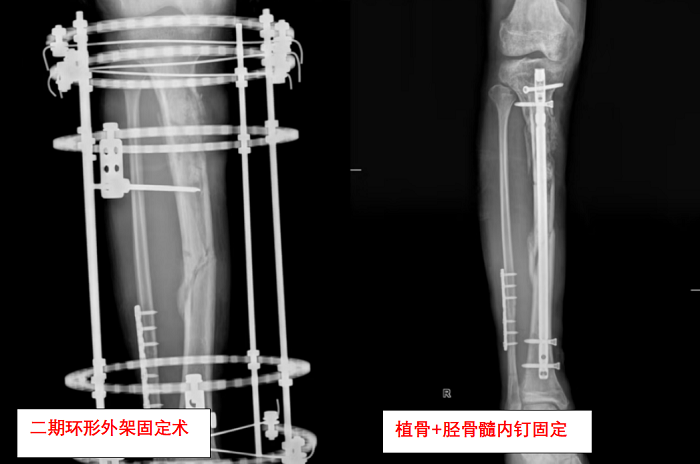

“第一次手術(shù)不是終點(diǎn),而是馬拉松的開始?!?創(chuàng)傷骨科副主任繆旭東說道。繆旭東介紹,黎先生的保肢之路遠(yuǎn)比想象艱難。由于創(chuàng)傷嚴(yán)重,黎先生先后經(jīng)歷了外支架固定術(shù):重建骨骼穩(wěn)定性;多次清創(chuàng)+植皮術(shù):對(duì)抗感染并修復(fù)軟組織;骨移植術(shù):填補(bǔ)缺損的骨組織; 功能重建術(shù):恢復(fù)關(guān)節(jié)活動(dòng)能力。

“每次手術(shù)都像在‘拆彈’?!笨碌戏逄寡裕腥?、骨不連、肌肉萎縮……任何一個(gè)環(huán)節(jié)失敗都可能前功盡棄。救治期間,營養(yǎng)科、康復(fù)科、心理科全程介入,定制營養(yǎng)方案、預(yù)防血栓、疏導(dǎo)焦慮。